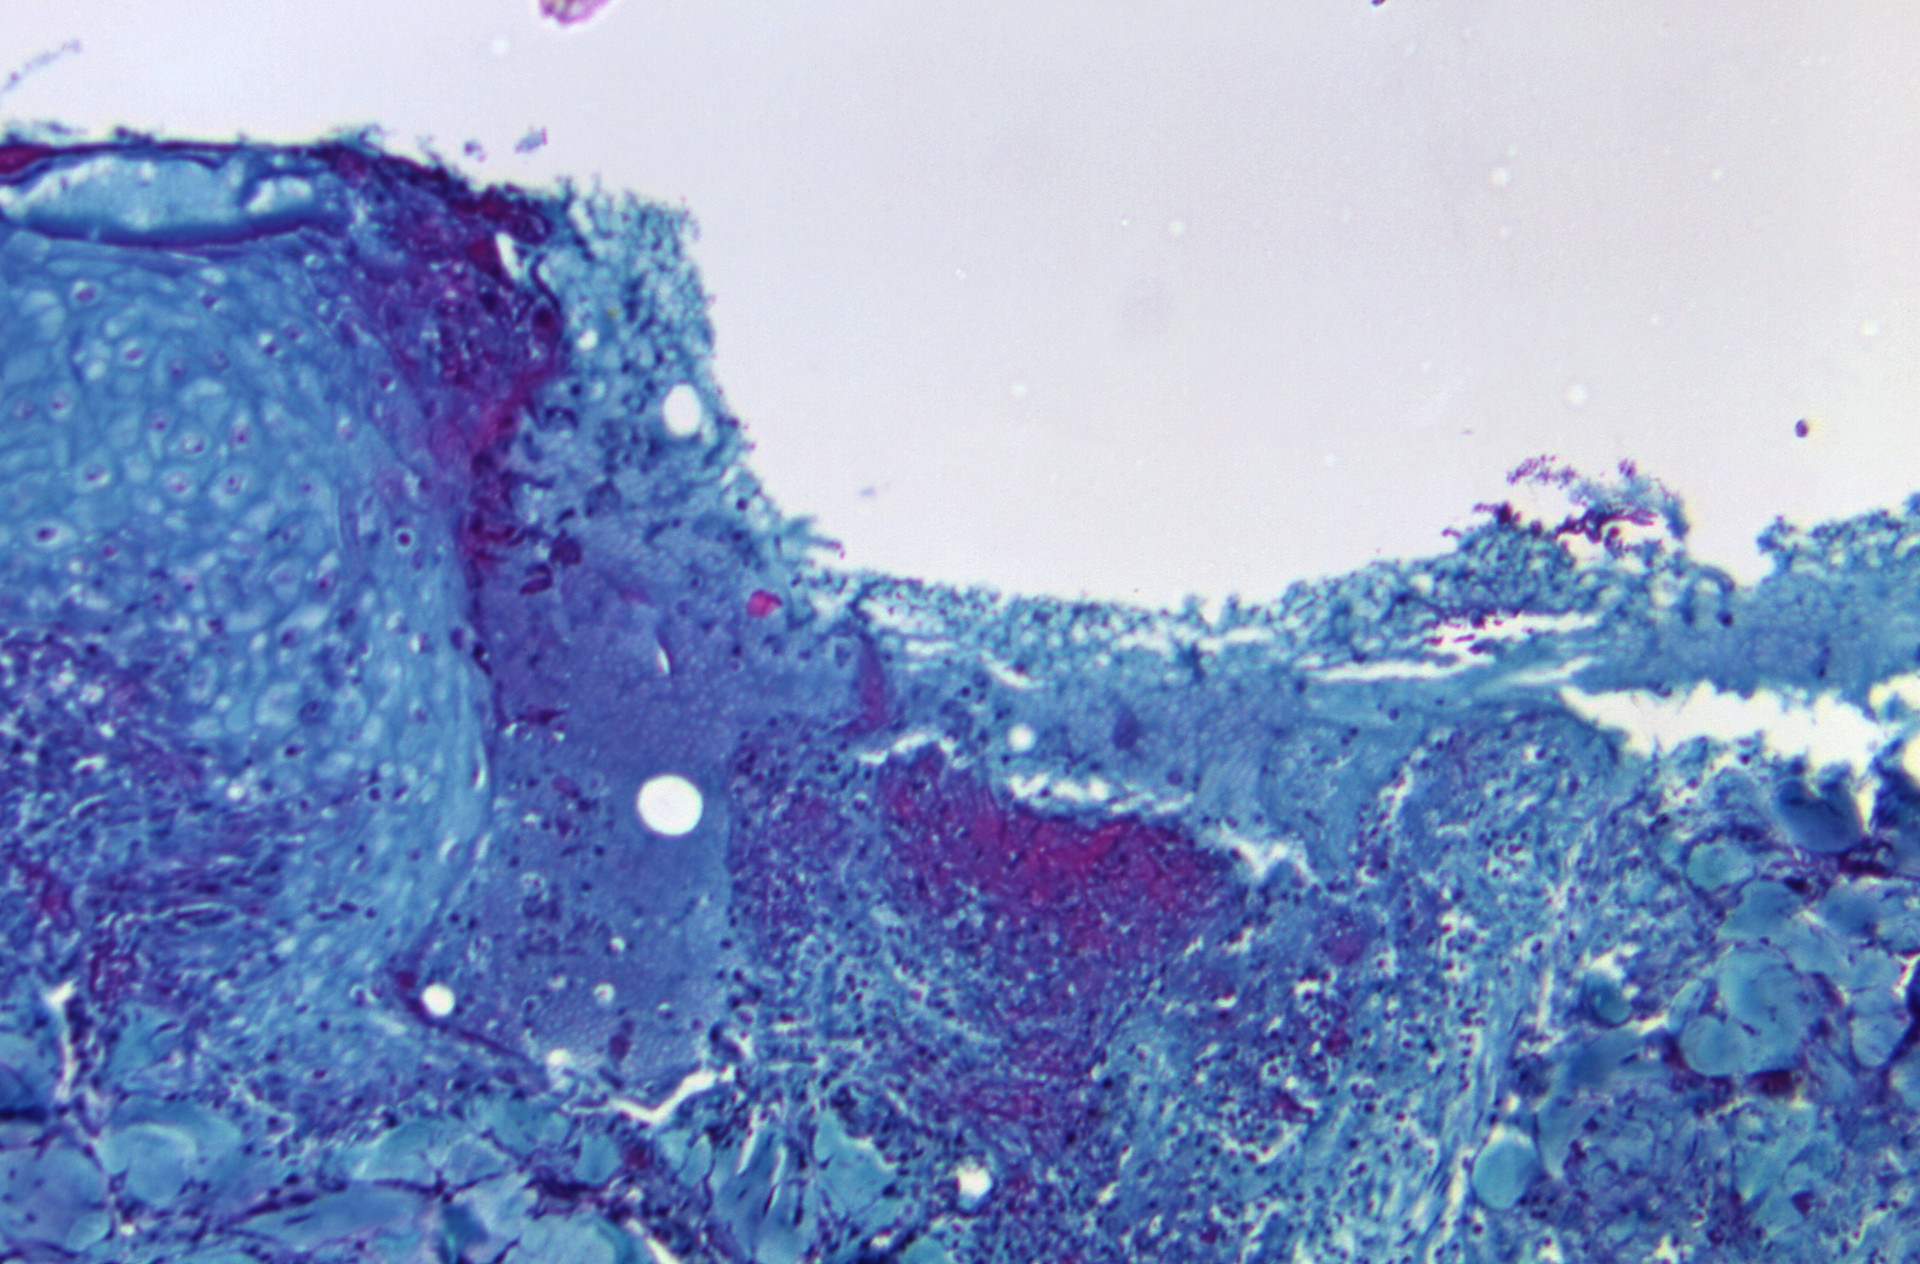

Monkeypox is in the same family of viruses as smallpox but generally causes a milder infection. It can be spread between people through direct contact with skin lesions or body fluids, or contaminated materials such as clothing or linens. It can also be spread through large respiratory droplets, which generally cannot travel more than a few feet, and prolonged face-to-face contact is required.